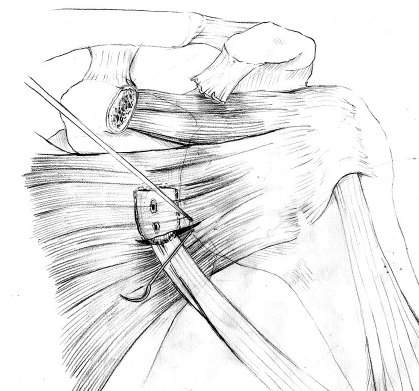

Transfer of coracoid process and conjoint tendon through subscapularis

Coracoid osteotomy

- use retractor on superior surface to identify entire coracoid

- release coracoacromial ligament from lateral coracoid

- release pectoralis minor from medial coracoid

- 2 cm coracoid osteotomy using 90o oscillating blade on microsagittal saw 100

- create bleed bone surface on posterior coracoid

- mobiize conjoint tendon, beware MCN 5 cm distal

Glenoid preparation

- split subscapularis at midsubstance of muscle belly

- can perform subscapularis tenotomy

- capsulotomy - vertical or transverse

- medial glenoid retractors / Fukuda retractor over humeral head

- inferior glenoid retractor - protect AXN

- create bleeding glenoid bone with burr

Secure coracoid

- inferior half of glenoid

- no medial overhang

- secure with 2 x bicortical screws with compression

Closure capsule / subscapularis